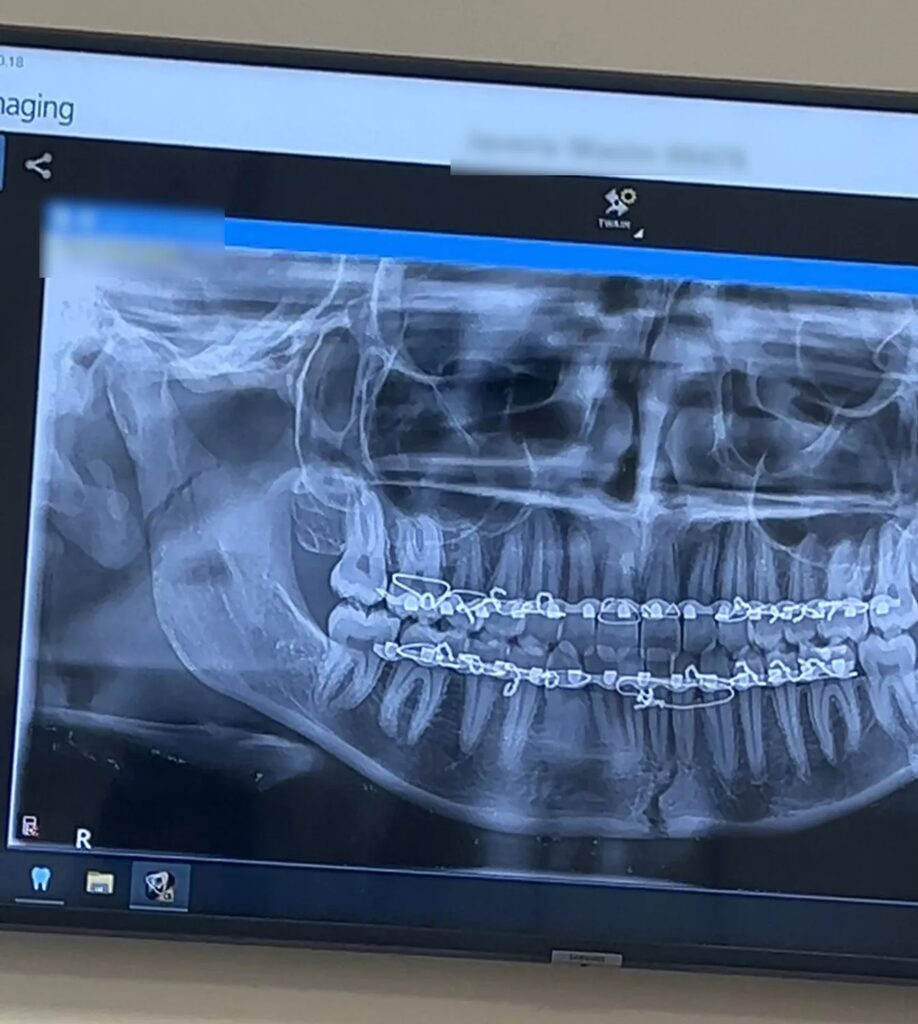

Στο νοσοκομείο, μια αξονική τομογραφία και ακτινογραφία επιβεβαίωσαν ότι είχε σπάσει τη γνάθο της σε δύο σημεία από το δάγκωμα της καραμέλας.

«Μου είπαν ότι η γνάθος μου ήταν σπασμένη και χρειαζόταν να την κλείσουν με σύρματα. Ήμουν σε σοκ. Νόμιζα ότι το μεγαλύτερο πρόβλημά μου ήταν το σπασμένο δόντι μου», λέει η Ουασίμ, η οποία έπρεπε να υποβληθεί σε εγχείρηση για να αποκατασταθεί η ζημιά. Η ανάρρωση περιλάμβανε το κλείσιμο της γνάθου με σύρματα για έξι εβδομάδες, κατά τη διάρκεια των οποίων ζούσε με υγρή διατροφή. «Δεν μπορώ να φάω τίποτα, το μόνο που τρώω είναι πρωτεϊνικά ροφήματα και σούπες», είπε στην εφημερίδα, προσθέτοντας ότι έχασε 7 κιλά τις πρώτες δύο εβδομάδες με τη γνάθο κλεισμένη με σύρματα.